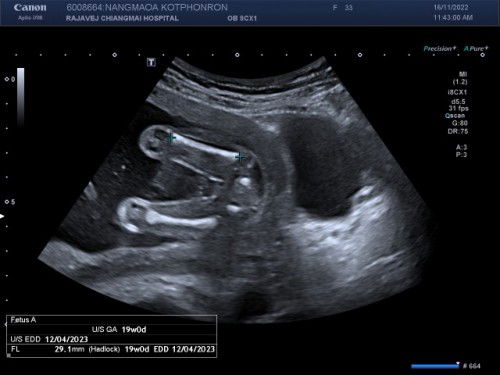

เด็กอ้วน 20 วีค ของแม่จ๋า

เมื่อไปซาวด์ดูเพศลุงหมอบอกว่าได้ลูกสาวนะครับ ก่อนท้องแม่หนัก 37.5 พอครบ 20 วีค แม่หนักแค่ 40.9 แต่ลุงหมอบอกหนูอ้วนท้วน นน.ตามเกณฑ์ดีค่ะ #ทีมเมษา2023 #ลูกคนแรก